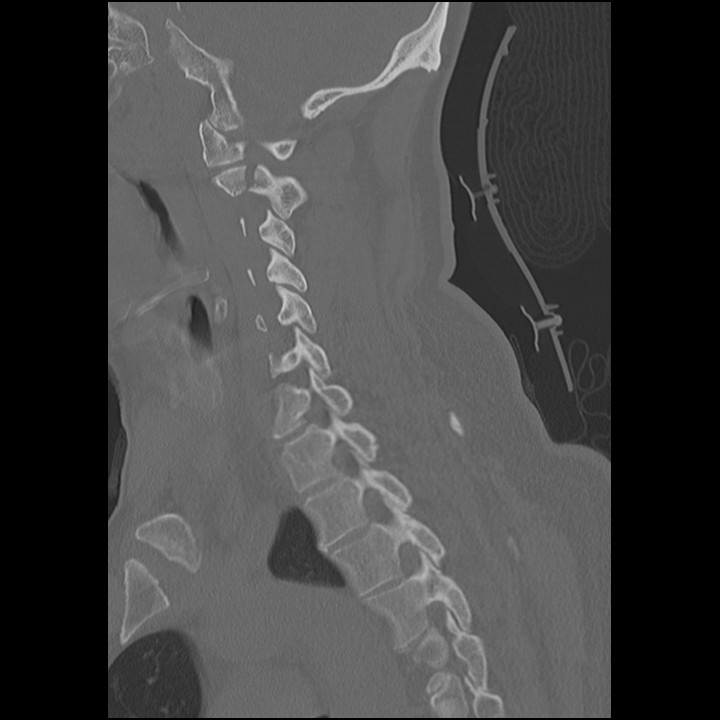

Given the particularly low sensitivity of X-ray when compared to CT in evaluating the cervical spine and the associated potentially significant consequences of missing an unstable fracture, CT is now the imaging modality of choice for initial imaging of the cervical spine in the trauma patient. When CT is not available or in specific patient populations (e.g. pediatrics), x-ray may be considered, paying particularly close attention to the adequacy of the images.

It is important to note that Xrays and CT scans of the cervical spine are unable to detect ligamentous injury. If there is concern for a ligamentous injury causing an unstable cervical spine despite a negative CT scan, an MRI should be performed. This should be done when patients have persistent neurologic deficits despite negative imaging.